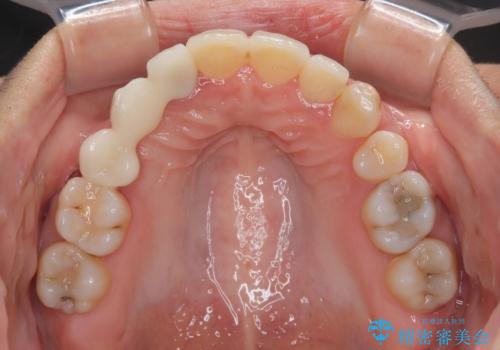

開咬と前突を改善 ワイヤー装置での抜歯矯正

- 口元の突出感と開咬を気にして来院された患者様です。

口元の突出感を改善するため、第一小臼歯を抜歯して口元を引っ込めることとしました。

一般的には上下左右の第一小臼歯4本を抜歯しますが、下顎に対して上顎が前方に位置しているため、まずは上顎小臼歯2本を抜歯し、治療経過を見て下顎小臼歯を抜歯するかどうかを決めていくこととしました。

元々むし歯の処置歯が多く、神経を取り除いている歯が多くありましたが、どうやら右上の前歯と小臼歯は外傷により神経を失った可能性があり、抜歯したスペース前後の歯が全く動かない状態でした。

結果として下顎の小臼歯は抜歯せず、右上の抜歯スペースはむし歯処置を兼ねてオールセラミックブリッジにて補綴治療を行うこととしました。

動かない歯での停滞や、出産と子育てなどにより治療期間は長期化しましたが、整った歯列にて仕上げることができました。